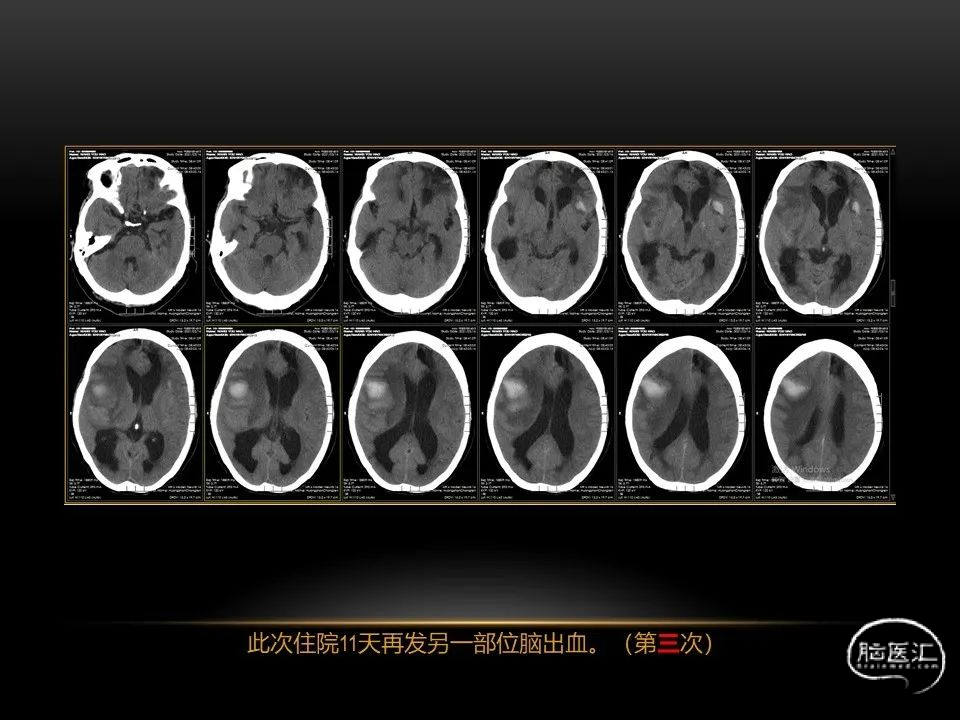

自发性脑出血临床上很常见,不同原因有特征性的出血部位。例如:基底节出血和丘脑出血大多是高血压性脑出血;脑叶出血,特别是多次复发的脑叶出血多见于老年人的脑血管淀粉样变。